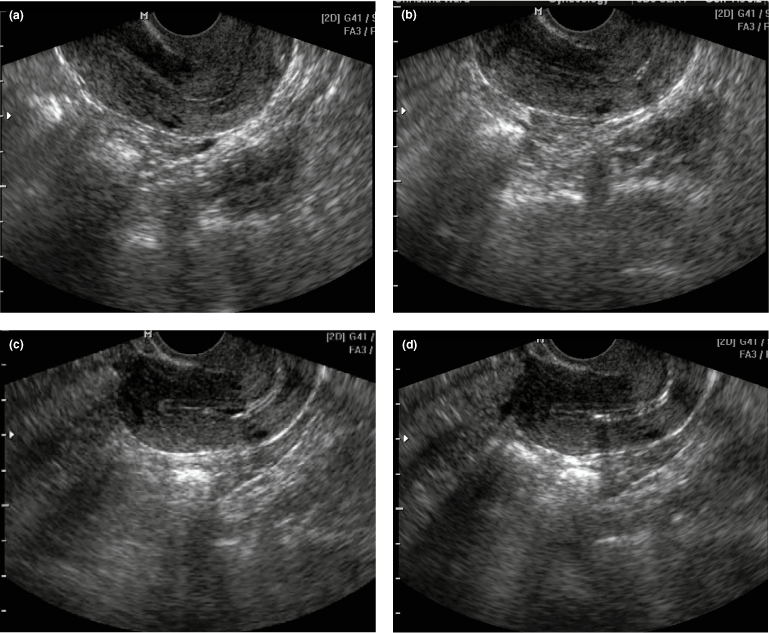

We identified 1268 first trimester ultrasound scans done at 6 (+1d) to 9 (+0d) weeks of gestation where gestational age at the day of the ultrasound could be precisely determined using the IVF dates . We calculated IVF dates by noting the number of days from fertilisation until the date of the ultrasound assessment .

Also the early scan isn't for dating because with IVF you know exactly how old the pregnancy is . You don't need a scan to determine dates . The first scan was to check implantation had occurred (rather than rely on blood test which might confuse a chemical pregnancy with actual pregnancy) and see heart beat all okay .